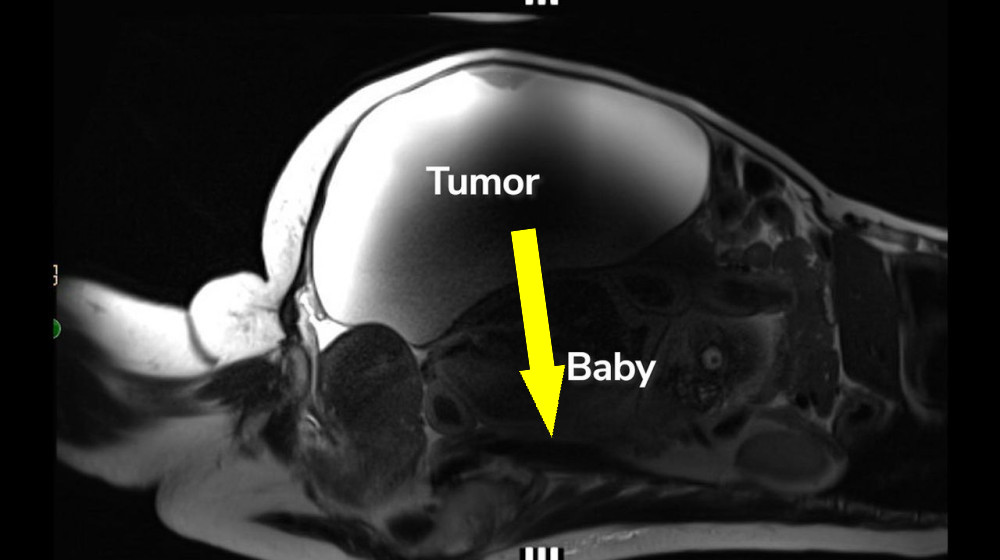

'Unprecedented': Woman delivers full-term abdominal pregnancy while also having 22-pound cyst removed

редкие случаи беременности

абдоминальная беременность

экстратеринная беременность